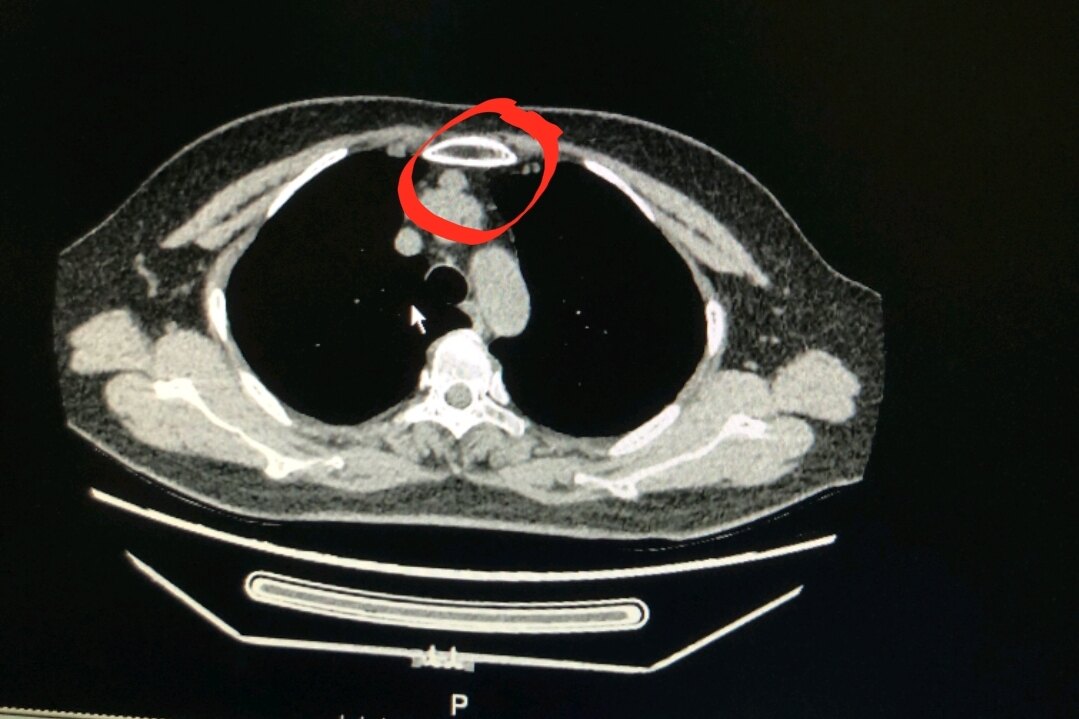

胸腺瘤/前纵隔占位/前纵隔结节/伴有肌无力是癌症吗?

图片尺寸859x519